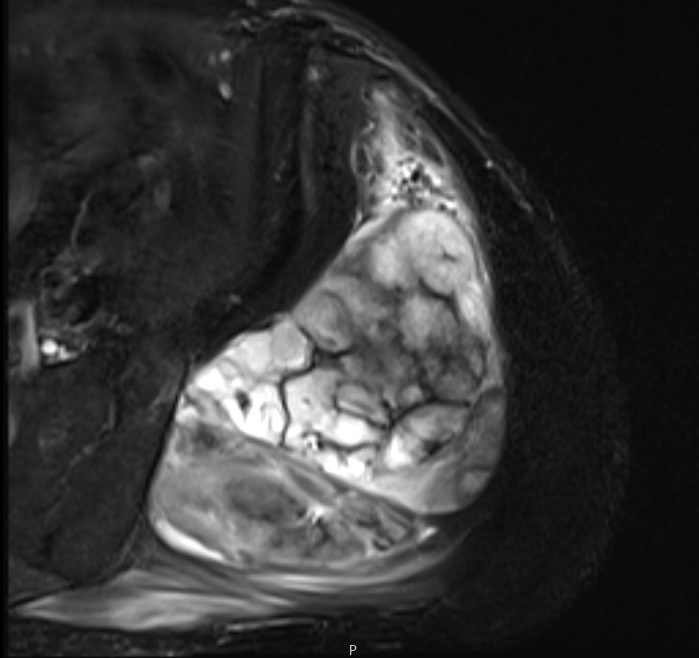

• Large encapsulated lipomatous mass with multiple thick internal trabeculations. (Fig. 1 – 13)

• High signal intensity both on T1-weighted and T2 weighted (Fig. 3)

Fig. 3 Axial fat suppressed T2-weighted MR image demonstrates a large heterogeneous mass with multiple thick internal trabeculations. Fatty areas suppress on T2 weighted fat suppressed areas